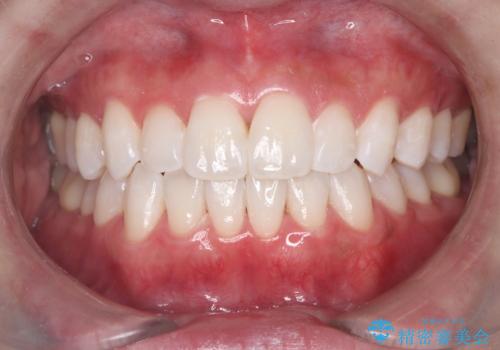

最新の症例

Latest cases